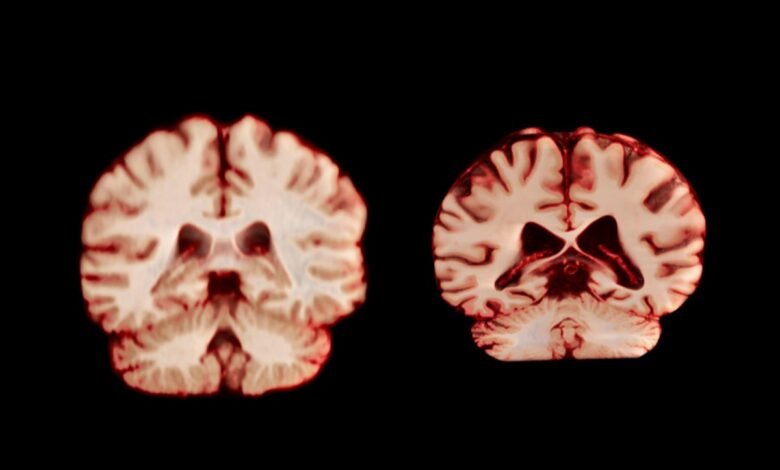

A healthy brain (left) and a brain affected by Alzheimer’s disease.

TheVisualMD/Science Source